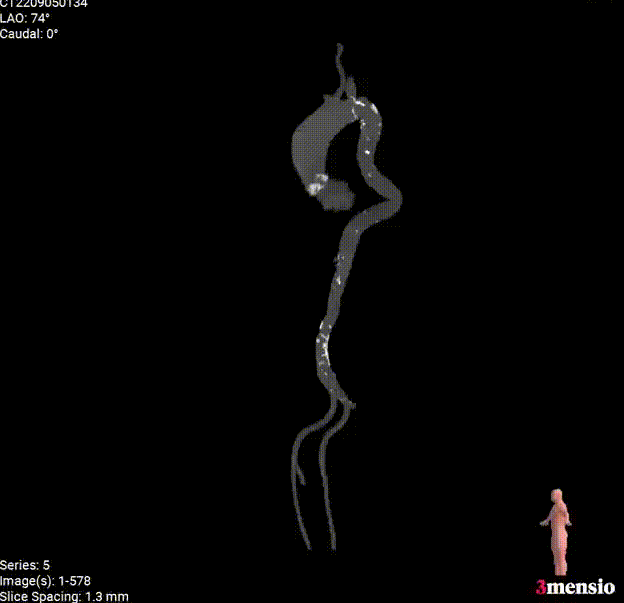

外周入路

◇ 外周入路血管走形迂曲,降主动脉有较锐夹角,主动脉弓,降主动脉,胸主动脉,腹主动脉有附壁钙化分布,血管内径可。